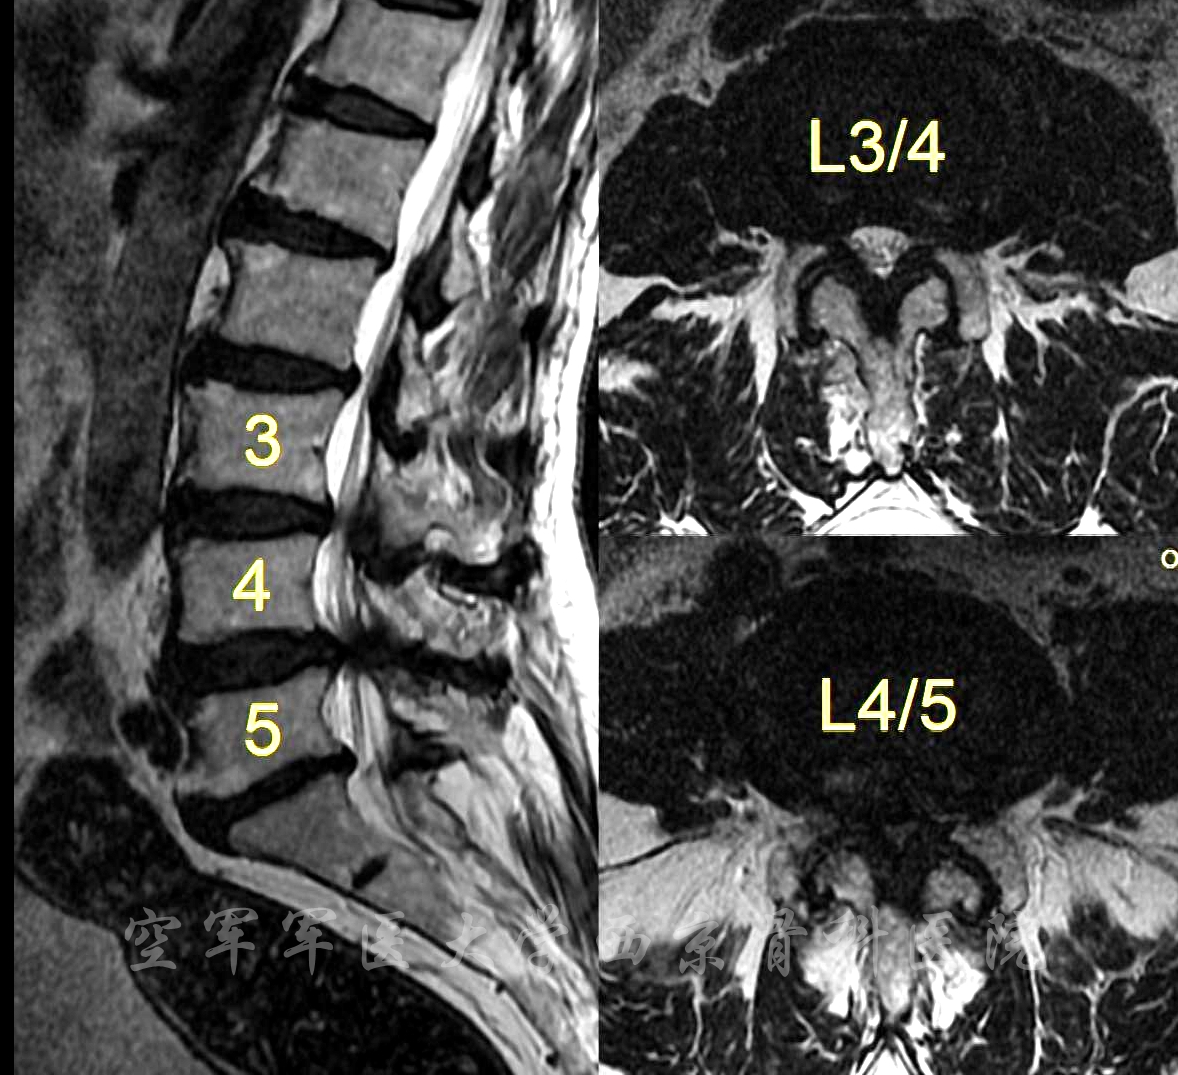

术前MRI

术前CT